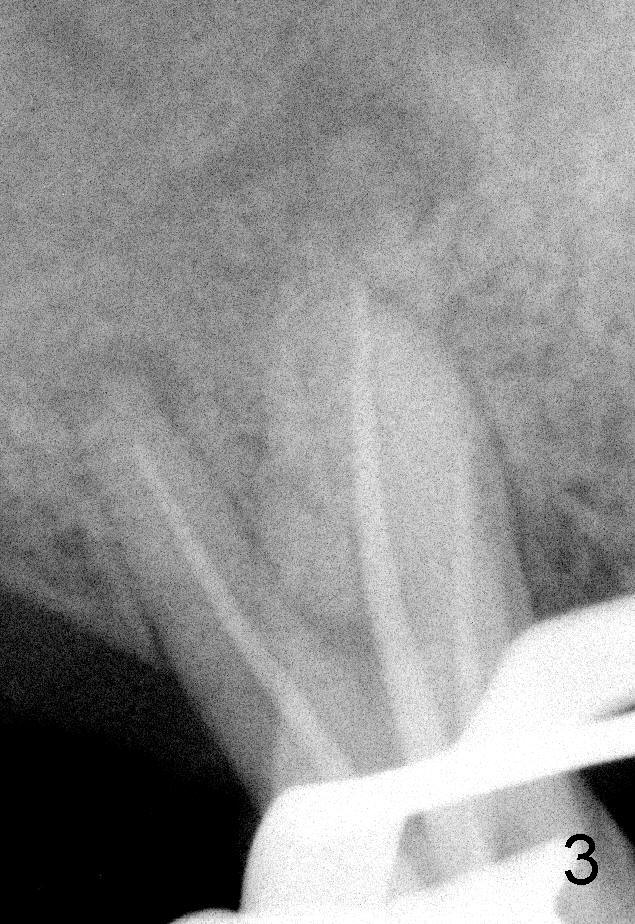

50岁男士有严重牙周炎(图一(2009年拍摄):二号牙(左上七)最终拔除(与图二对比)),最近三号牙(左上六)冷热痛,而且不能咬东西,三号牙多处牙周袋深,根尖片显示远中颊侧和腭侧根尖阴影(图二箭头),初步诊断:牙周牙髓综合症,需要根管治疗以及牙周手术,还可能保留不了。开髓表明活髓,近中颊侧和远中颊侧(DB)根管口很接近(参考图一图二),扩大(30/.04)后并表现不出来(图五至图七),开始近中根管口好像比较接近腭侧根管口,以为是MB2,使用Piezo超声波/diamond tip在MB(图六*)颊侧和近中寻找另外一个根管(箭头),但不成功。腭侧根管扩大到40/.06,匆匆忙忙插入主牙胶尖,拍摄根尖片(图三),显示远中颊侧以及腭侧(P)牙胶尖在相应牙根正中,但是近中颊侧并不是这样(图四=图三+MB牙根和牙胶尖轮廓),这说明还存在另外一个根管。经过再次合适扩大(crown down),腭侧牙胶尖进入更深地方(临床上),这时病人已经坐立不安了,paper points吸干根管后,拍摄图五至图七,暂封。由于病人还缺失好几颗牙齿,劝他去拍摄CT。今天术后第五六天,打电话给他,他很高兴,说冷热痛消失,牙齿也牢靠多了,但是还没去拍摄CT。下周三他回来完成根管治疗。

如果他还没有CT,我该怎么在没有外科显微镜下找遗留根管呢?MB和P根管口之间的确有一个沟(map),但是非常光滑(图五至图七),能找到根管口?还是往原来MB根管口颊侧探索?图三/图四暗示MB1还没有被发掘,对吗?MB2存在吗?